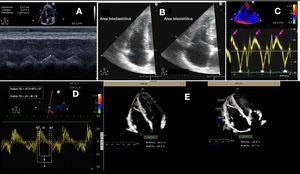

A. Variación de la vena cava inferior. Se muestra la imagen en 2D de inspiración y espiración y en modo M; B. Doppler continuo de la insuficiencia tricuspídea. La flecha roja señala la velocidad máxima de la insuficiencia tricuspídea; C. Tiempo de relajación isovolumétrica (TRIV); D. Tiempo de aceleración de la arteria pulmonar (Tac); E. Doppler pulsado de la insuficiencia pulmonar; las fechas señalan la velocidad máxima protodiastólica del flujo de la insuficiencia pulmonar (VIPpd) y la velocidad máxima del flujo de la insuficiencia pulmonar en telediástole (VIPtd); F. Flujo pulmonar tipo I normal con ascenso y descenso simétrico; G. Flujo de la arteria pulmonar tipo I, con flujo triangular simétrico, flujo normal; H. Flujo pulmonar tipo II con flujo triangular asimétrico, sugiere aumento de presión pulmonar; I. Flujo pulmonar tipo III, con la flecha que señala la incisura mesosistólica por cierre precoz de la válvula pulmonar.

La PAD se calcula mediante la PVC y su estimación se puede realizar mediante los siguientes parámetros:

Índice de colapso de la vena cava inferior (VCI). Se mide la VCI en el plano subcostal a 1-2cm de su unión con la AD, detrás de la vena hepática, en decúbito supino y al final de la espiración. El IC=[Dmax VCI- Dmin VCI]/Dmax VCI). En el paciente crítico hay situaciones donde la dilatación de la VCI sin colapso respiratorio no predice respuesta al aporte de cristaloides44 (fig. 4A).

Cociente E/e’ tricuspídeo. Mediante PW se registra la velocidad protodiastólica de llenado a nivel de la válvula tricúspide (onda E) y por DTI se registra la velocidad de relajación de la pared lateral del anillo tricuspídeo en protodiástole (onda e’). Un cociente E/e’>6 demostró asociarse a una PAD elevada:>10mmHg25. Validado en pacientes ventilados13.

Patrón de flujo de las venas hepáticas: Una relación de ondas S<D se asocia con PAD elevada13,25.

Presión sistólica de la arteria pulmonar (PAPs)Mediante Doppler color se registra la IT, se coloca el cursor del Doppler de onda continua (CW) con buena alineación para calcular la velocidad máxima de la IT (VmaxIT), la cual equivale al gradiente de presión entre AD y VD. En situaciones de IT masiva, la fórmula no es aplicable ya que el componente inercial no es despreciable. PAPs=4×Vmax IT2+PAD (fig. 4B).

TRIV. Se debe colocar el DTI con la muestra a nivel de la pared libre del VD en la válvula tricúspide (fig. 4C).

Tiempo de aceleración de la arteria pulmonar (Tac), que es el intervalo de tiempo desde el inicio de la eyección del VD hasta el pico de velocidad de flujo a través de la válvula pulmonar (fig. 4D-G). En el signo de 60/60 se asocia un Tac<60 con un gradiente sistólico tricuspídeo mayor de 30, pero menor de 60mmHg.

Se calcula la velocidad pico de la IP en telediástole (VIPtd) en el plano paraesternal eje corto a nivel de grandes vasos (fig. 4E). Este método es impreciso en presencia de IT masiva.

Resistencias vasculares pulmonares (RVP)Para una medición cuantitativa de las resistencias vasculares pulmonares (RVP) se deben relacionar dos mediciones, la VmaxIT por CW y la integral velocidad-tiempo del tracto de salida del VD (IVTTVSD) mediante PW (fig. 4). Se cuantifica en unidades Woods. RVP=VmaxIT / IVTTSVD×10+0,16.

También se pueden evaluar las RVP de forma semicuantitativa observando la presencia de «muescas» en el espectro PW de la velocidad de flujo en el tracto de salida del VD (fig. 4F-H). Una muesca mesosistólica es indicativa de HTP grave (fig. 4I).

Aplicaciones clínicas en cuidados intensivosLa disfunción aguda del VD es un síndrome heterogéneo, consecuencia de un desacoplamiento entre el VD-AP secundario a entidades con alta incidencia en el paciente crítico4. El desacoplamiento VD-AP se observa generalmente en casos de un rápido aumento de la PAP, en casos de HTP en etapa terminal y con una HTP leve en pacientes con estados inflamatorios pulmonares como SDRA, sepsis e insuficiencia ventricular izquierda, todas ellas condiciones que también están asociadas con efectos inotrópicos negativos. Además, en muchas de estas condiciones los pacientes estarán sometidos a VM, pudiendo intensificar o incluso causar per se un fracaso del VD al provocar un aumento de las RVP. Cuando la VM es usada en pacientes sin patologías cardiorrespiratorias, el volumen corriente no tiene consecuencias hemodinámicas deletéreas. Sin embargo, en presencia de lesión pulmonar, el aumento de la presión transpulmonar aumenta la poscarga del VD y reduce el Tac (fig. 4G).